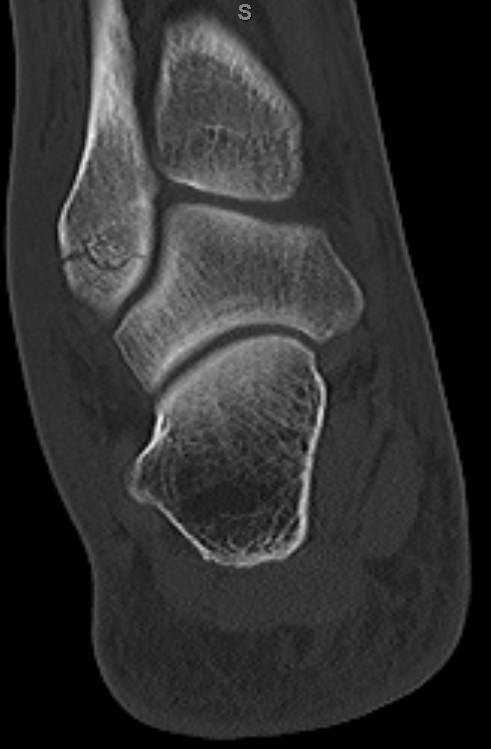

Well, just corrected my thread title to reflect broken FIBULA (smaller bone on the outside of the ankle), not tibia (the big one in the middle). Doctor misspoke; went back and looked at the CT scans and indeed the fracture can be seen on the CT scan ( I do not have a copy of the x rays).